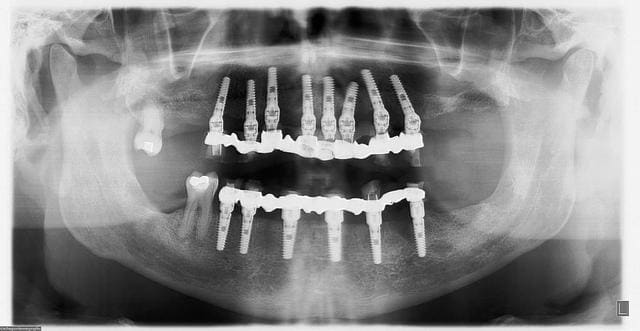

pano de contrôle à 10 jours post op...

tout va bien, aucune douleur, juste une petite correction de hauteur des incisives sup pour la phonation (les F)...;-)